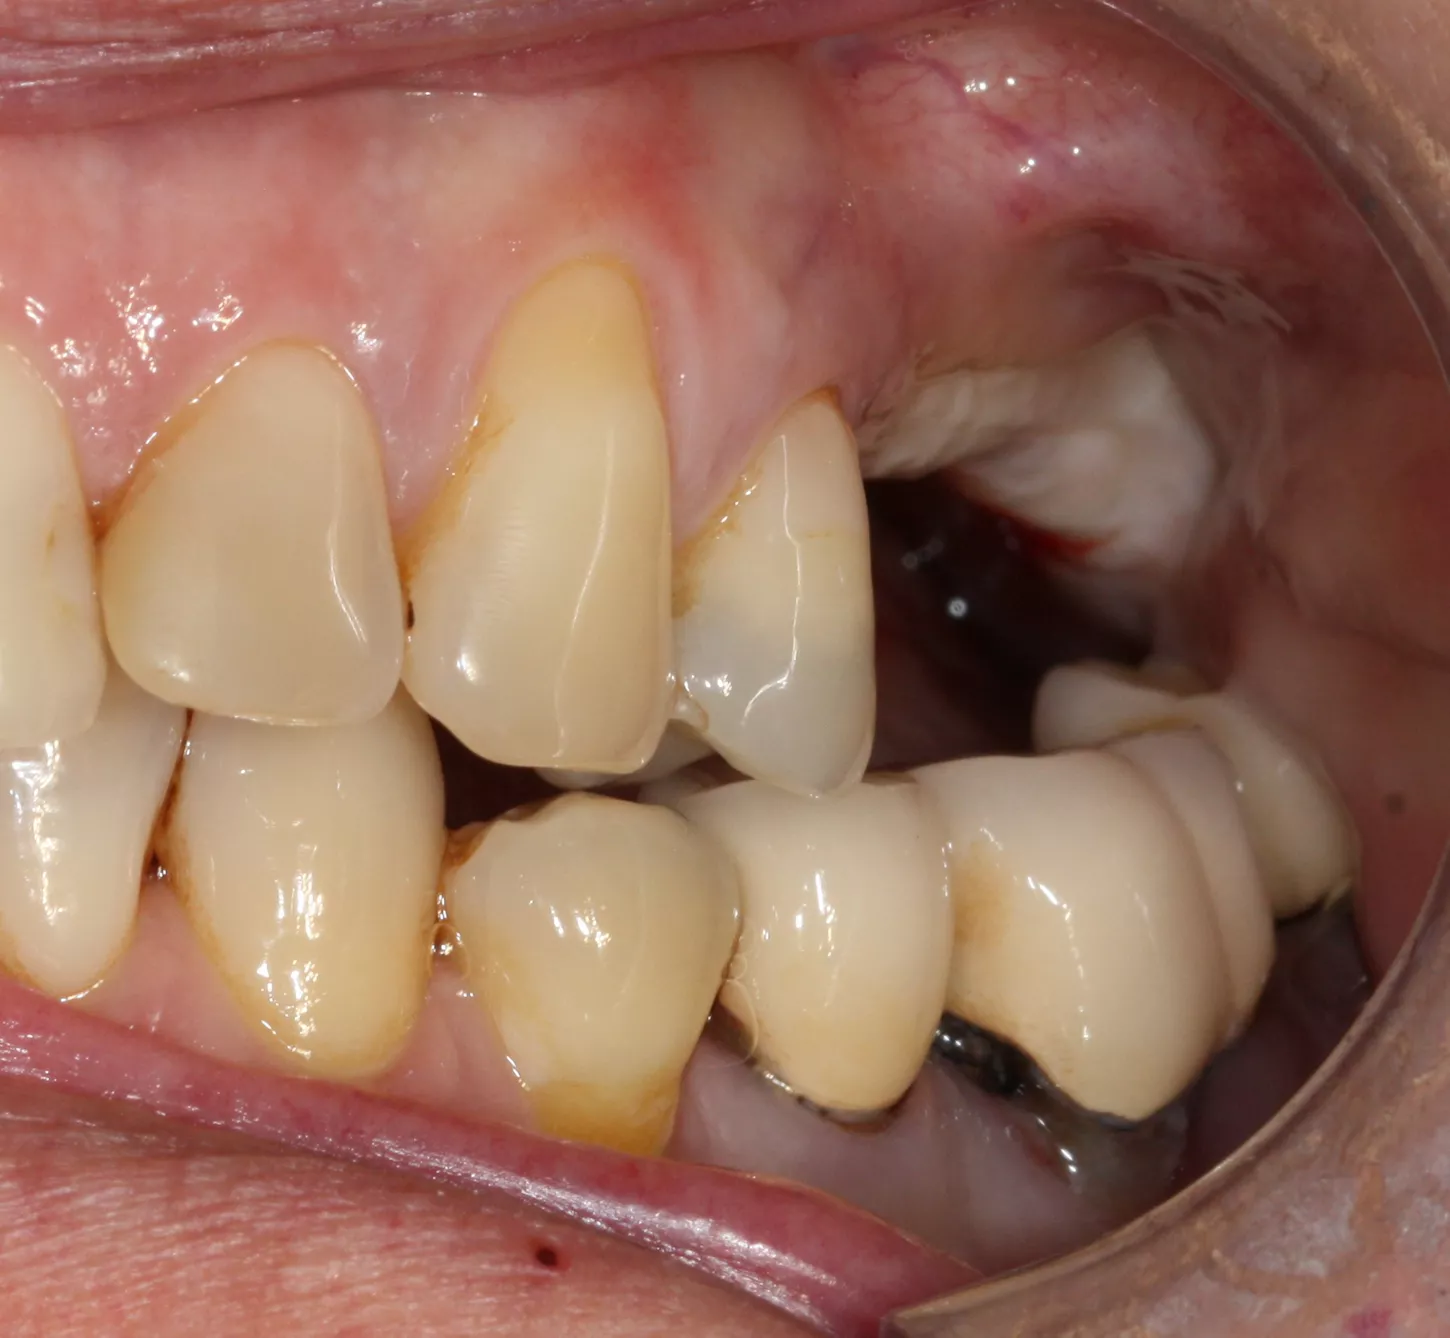

Two single-unit zirconia-veneered Simeda® crowns were fabricated on titanium bases.

19. Final prosthesis in the mouth 3 years post implant placement.